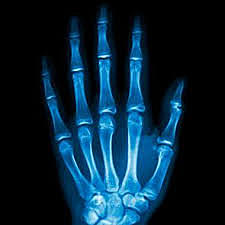

• Descubrimiento

Descubrimiento

Wihelm Conrad Roetgen fue quien descubrió los rayos x mientras experimentaba con tubos vacios y un generador eléctrico.